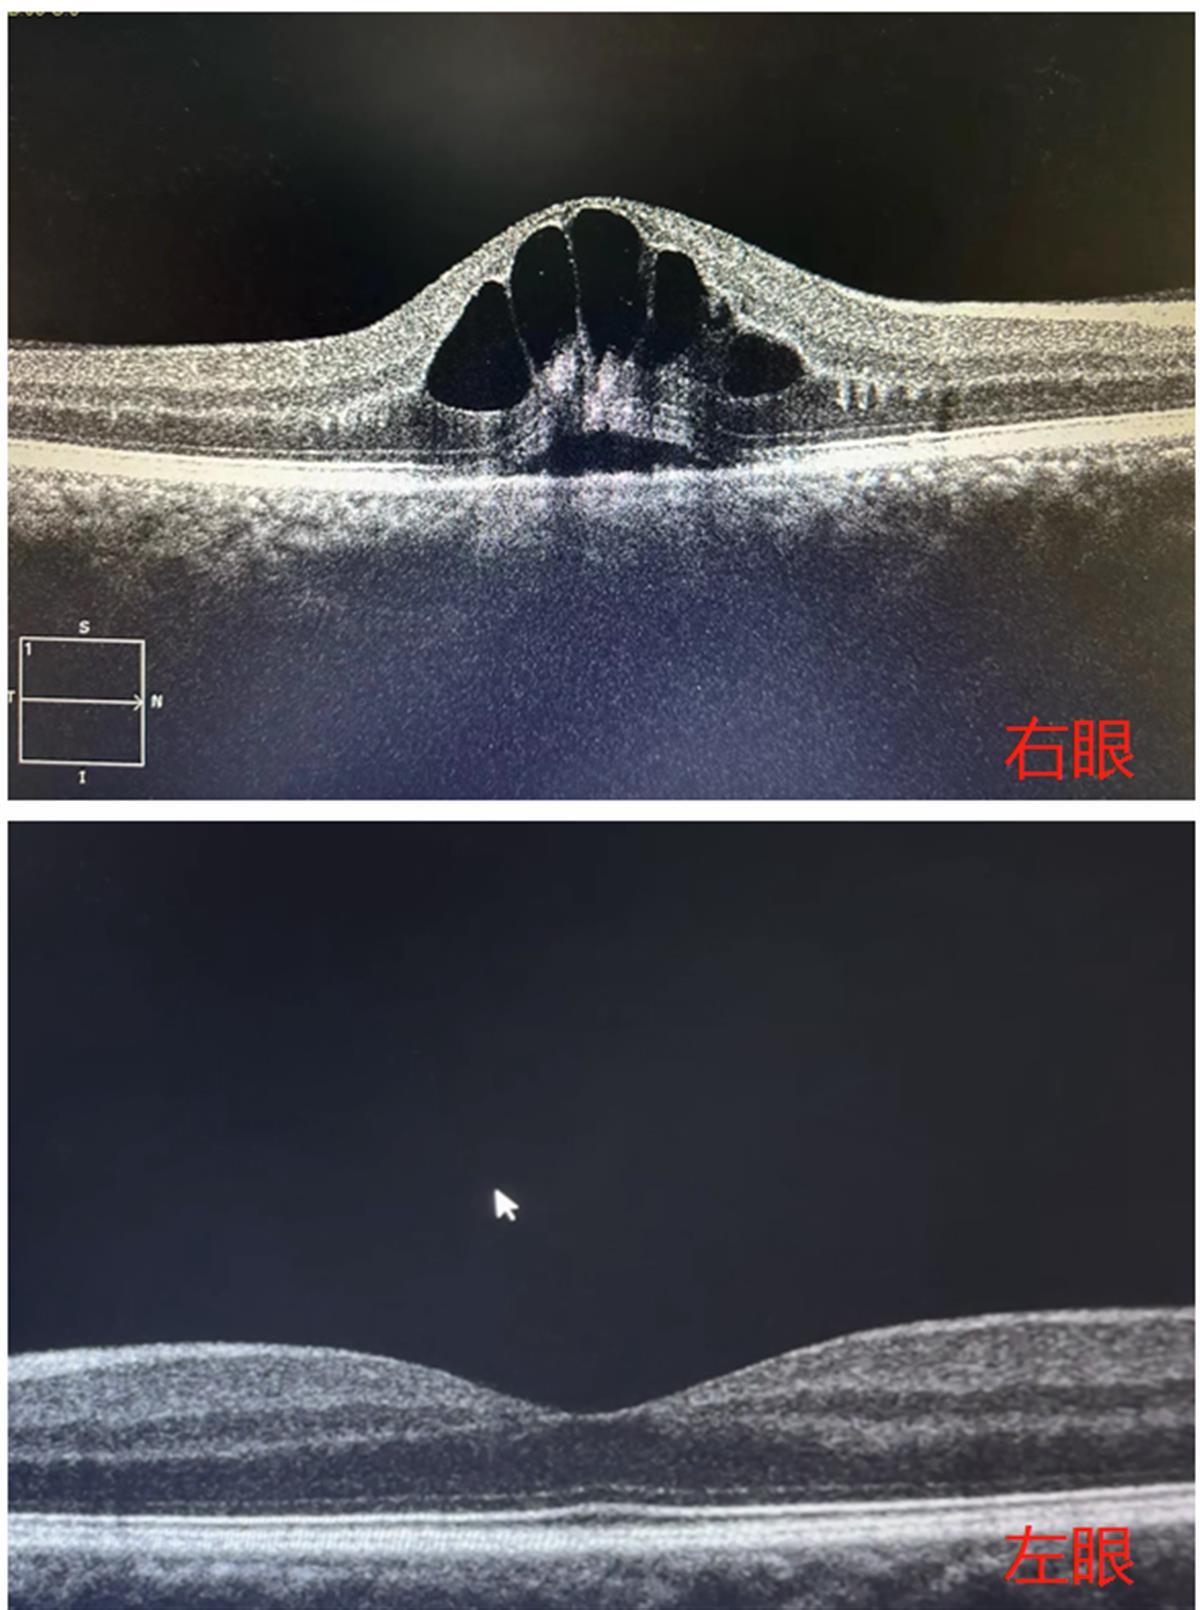

检查可见,眼底黄斑区出现“花瓣”状囊样水肿

经该院眼底病科主治医师杨兰仔细检查,刘先生右眼视力仅为0.3。在问诊过程中得知刘先生有高血压病史,但平时并未进行治疗和干预。于是杨兰立刻为其安排了血压检查,检查结果显示刘先生血压高达162/115mmHg(正常血压值为90-140mmHg)。进一步检查发现,刘先生眼底黄斑区出血及渗透,出现花瓣状囊样水肿,被诊断为“右眼视网膜静脉阻塞”,需要及时进行降血压的治疗后,再完善眼底造影检查,以便进一步治疗。